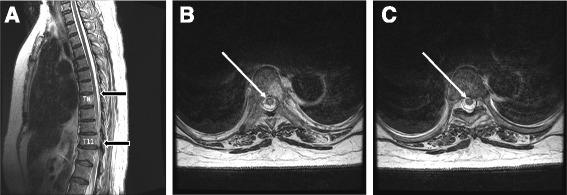

A 75-year-old woman underwent a scheduled abdominal total hysterectomy and bilateral salpingo-oophorectomy for suspected endometrial cancer. In the operating room, an epidural catheter was inserted at T11/12 while the patient was conscious. The needle entered smoothly, with no observed bleeding, paresthesia, or pain, and general anesthesia was induced. During surgery, 4 mL of 0.25% levobupivacaine and 0.1 mg of fentanyl were administered via the epidural catheter, and a solution of 2.5 μg/mL fentanyl and 0.2% levobupivacaine was continuously infused at 4 mL/h for postoperative analgesia. The patient promptly regained consciousness and could move her bilateral lower extremities without difficulty upon leaving the operating room. During the first postoperative night, she complained of an absence of sensation and weakness in the lower extremities. By the morning of the second postoperative day, she had developed paralysis and sensory losses associated with touch, temperature, pinprick, and vibration below T5. The epidural infusion was stopped. Magnetic resonance imaging (MRI) revealed a hyperintense area of the thoracic cord from T8 to T11, and spinal cord infarction was suspected. Ossification of the yellow spinal ligaments between T11 and T12, resulting in thoracic canal stenosis and thoracic spinal cord compression, were observed. Notably, the epidural catheter was inserted at the same site where the thoracic canal stenosis was present.

一名75岁女性因疑似子宫内膜癌接受了计划性腹式全子宫切除术及双侧输卵管卵巢切除术。在手术室,患者清醒时于T11/12置入硬膜外导管。穿刺针顺利进入,未见出血、感觉异常或疼痛,随后诱导全身麻醉。手术期间,经硬膜外导管给予4毫升0.25%左旋布比卡因和0.1毫克芬太尼,并以4毫升/小时的速度持续输注2.5微克/毫升芬太尼和0.2%左旋布比卡因溶液用于术后镇痛。患者离开手术室后迅速苏醒,双侧下肢活动自如。术后第一个晚上,她诉说下肢感觉缺失和无力。术后第二天早晨,她出现了T5以下与触觉、温度觉、针刺觉和振动觉相关的瘫痪和感觉丧失。停止硬膜外输注。磁共振成像(MRI)显示T8至T11胸段脊髓有高信号区,怀疑为脊髓梗死。观察到T11和T12之间的黄韧带骨化,导致胸段椎管狭窄和胸段脊髓受压。值得注意的是,硬膜外导管插入的部位正是存在胸段椎管狭窄的部位。